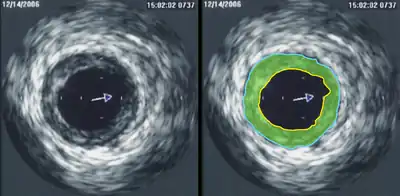

![]() An abnormal echocardiogram: Image shows a midmuscular ventricular septal defect. The trace in the lower left shows the cardiac cycle and the red mark the time in the cardiac cycle when the image was captured. Colors are used to represent the velocity and direction of blood flow. | |